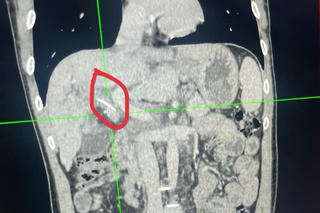

Phẫu thuật cấp cứu trường hợp dị vật xuyên thành bụng do máy bắn đinh